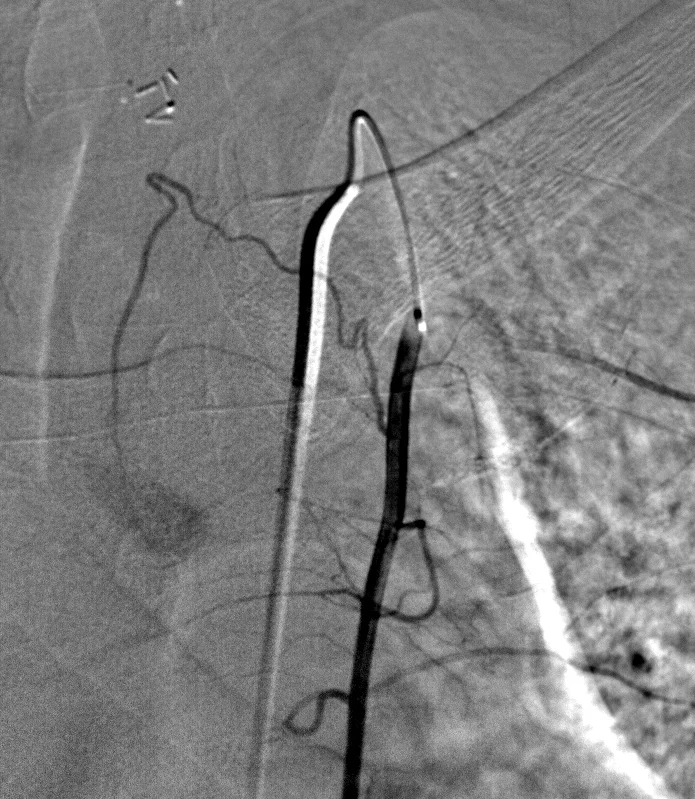

Visceral Embolization: Case 5

37 year old male with recurrent hyperparathyroidism after parathyroidectomy.